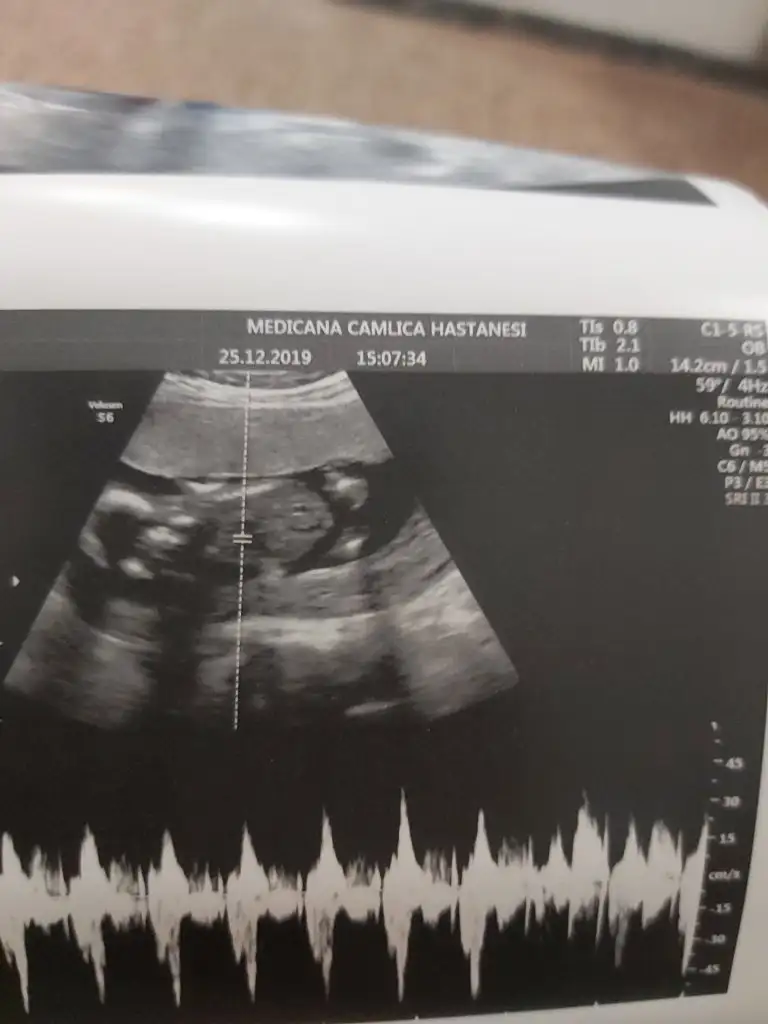

dr soylemeden siz gorun genital nub teorisi ( bebegin cinsiyeti)

Siz de yine bakarmısınız net söyledi kız diye herkes erkek demişti sizin gibi bende öyle diyordum ama ters köşe yaptı galiba bizimki çok hareketliydi 🤭🤣

• 20191225_151558.webp

20191225_151558.webp

20,2 KB · Görüntüleme: 46